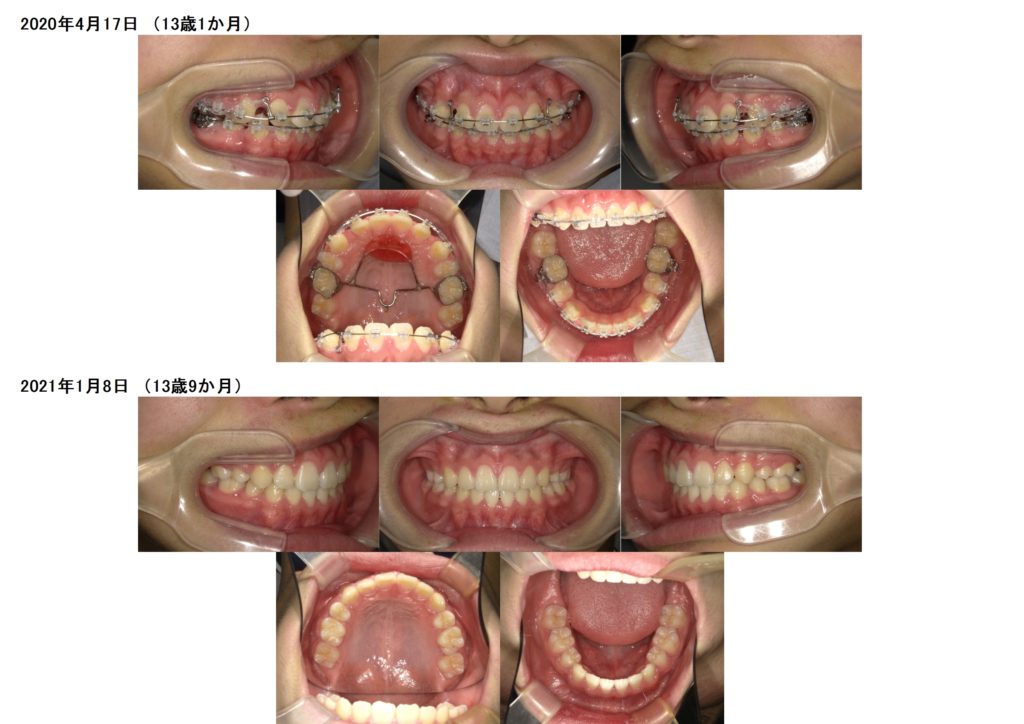

↑この患者様は上下の歯を2本ずつ抜歯しています。

上の顎にアンカースクリューを使用し、抜歯した際に6番目の歯が寄ってこないためにしています。

このように土台を整えつつ、ブラケットを使用し調整をしていきます。

奥歯の噛み合わせを確立したら、あとは前歯部の噛み合わせを合わせ引っ込めていきますよ

隙間が埋まったら治療が終わりです☆

↑治療前、治療後の口腔内写真の比較です。

上下の顎のアーチを整えながら、抜歯した隙間を利用し噛み合わせの深さや突出している部分も改善しているのが分かると思います。

約2年間のブラケット治療になりますが、お口の中もとても変化します。突出している方だと横顔のラインも変わりますので、